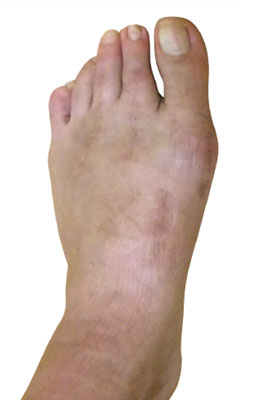

Before

Lapidus Forever Bunionectomy™ and Hammertoe Correction before

After

Lapidus Forever Bunionectomy™ and Hammertoe Correction after

Lapidus Forever Bunionectomy™ and Hammertoe Correction

George is a 62-year-old businessman who presented with a sore on his second toe from rubbing on his shoes. We decided to correct his foot as a whole and performed several orthopedic surgical procedures as she had both types of bunions. He chose our Lapidus Forever Bunionectomy™, a hammertoe correction and an osteotomy for his Tailor’s Bunion (bunionette). George was weight bearing on his foot at two weeks and back in regular shoes at 8 weeks with no pain and full function.

Lapidus Forever Bunionectomy™ and Hamertoe Correction before

Lapidus Forever Bunionectomy™ and Hamertoe Correction after

Lapidus Forever Bunionectomy™ and Hamertoe Correction

Amanda is a 37-year-old mother who could not take much time off her foot and needed correction of a very large bunion (hallux valgus) that had also resulted in a hammertoe and partial discoloration of the 2nd toe joint. Amanda had a Lapidus Forever Bunionectomy™ and was back on her foot at 2 weeks after surgery and able to take care of her young children while she healed. Her bunion correction results are amazing, and her foot is fully back to normal.